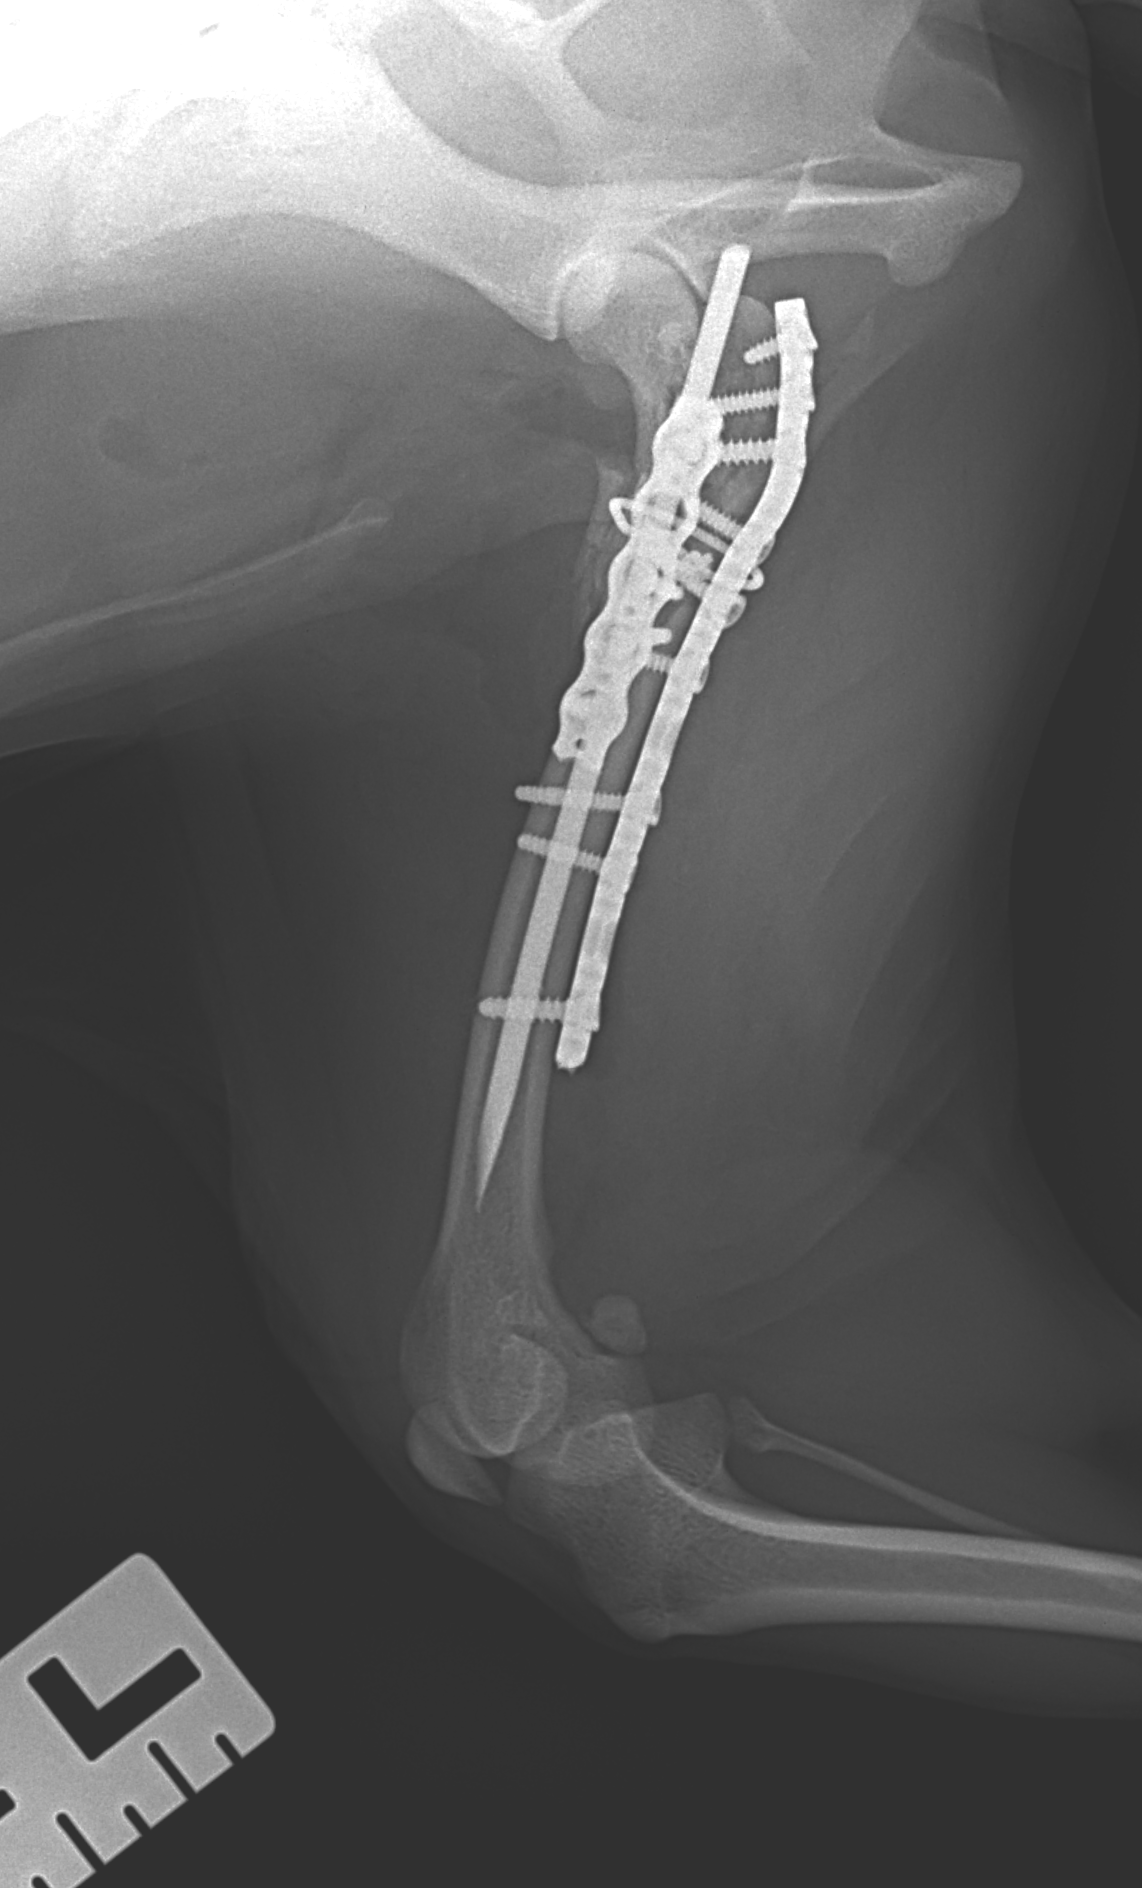

大腿骨近位粉砕骨折

10歳の高齢犬が、大腿骨近位を粉砕骨折して紹介来院しました。高齢で手術リスクが高くさらに骨片が多く安定性が確保しづらい症例でしたが、プレート&ロッド法と直交プレート法を組み合わせ、しっかりと固定しました。これにより強い安定性が得られ、早期のリハビリも可能になります。今後も痛み管理とリハビリを徹底し、再び元気に歩ける日を目指します。